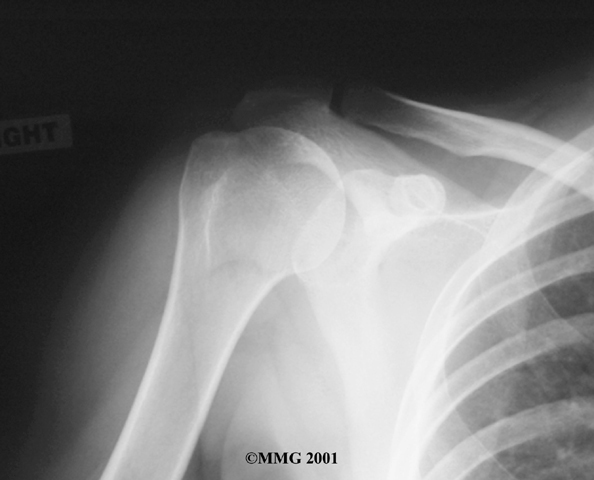

Your doctor may want to take X-rays of the AC joint. X-rays can show narrowing of the joint and bone spurs around the joint, which are signs of degeneration.

X-Rays